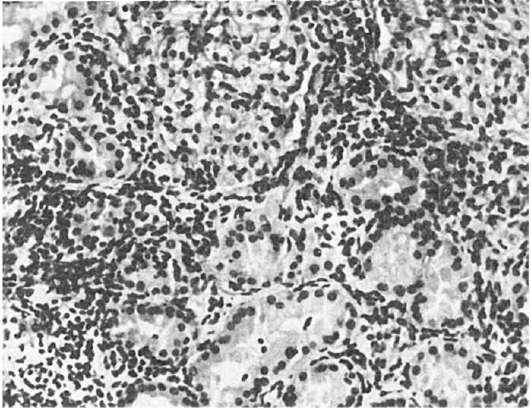

Рис.

233. Острый тубуло-интерстициальный нефрит

нулем - гранулематозный вариант. Клеточный инфильтрат располагается периваскулярно и, проникая в межканальцевые пространства, разрушает нефроциты (рис. 233). Некротические изменения нефроцитов сочетаются с дистрофическими. На базальной мембране канальцев выявляются компоненты иммунных комплексов (IgG, IgM и С3).